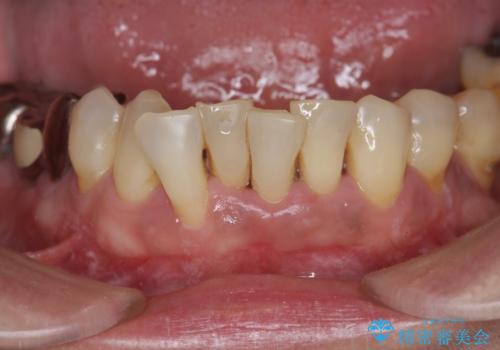

- 下顎前歯のグラつきがどんどん悪くなり、痛くて噛めなくなってきたことの改善を希望され来院されました。

下顎前歯の1本は前歯よりも前に出てしまい後ろからの力を受けることで、周囲の骨も吸収しグラつきも大きくみられます。

矯正治療を行うことで、歯を削ったり(ブリッジ)、手術の必要(インプラント)なく機能を欠損部位を無くし機能回復を達成することができました。